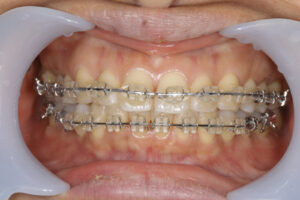

Invisalign failed orthodontic treatment

前歯が噛んでいない

Invisalign failed

奥歯が噛んでいない

Invisalign correction failure

orthodontic treatment

表側矯正での再治療

治療方針

インビザラインと歯周病の相性はよくありません。

それは、インビザラインの着脱で歯が揺り動かされる事とアタッチメントの下は磨けないからです。

そのため、歯周病を悪化させる方向になってしまいます。

歯周病治療の場合、表側のワイヤー矯正をお勧めします。

それは、まだ歯磨きがやりやすい矯正になるからです。